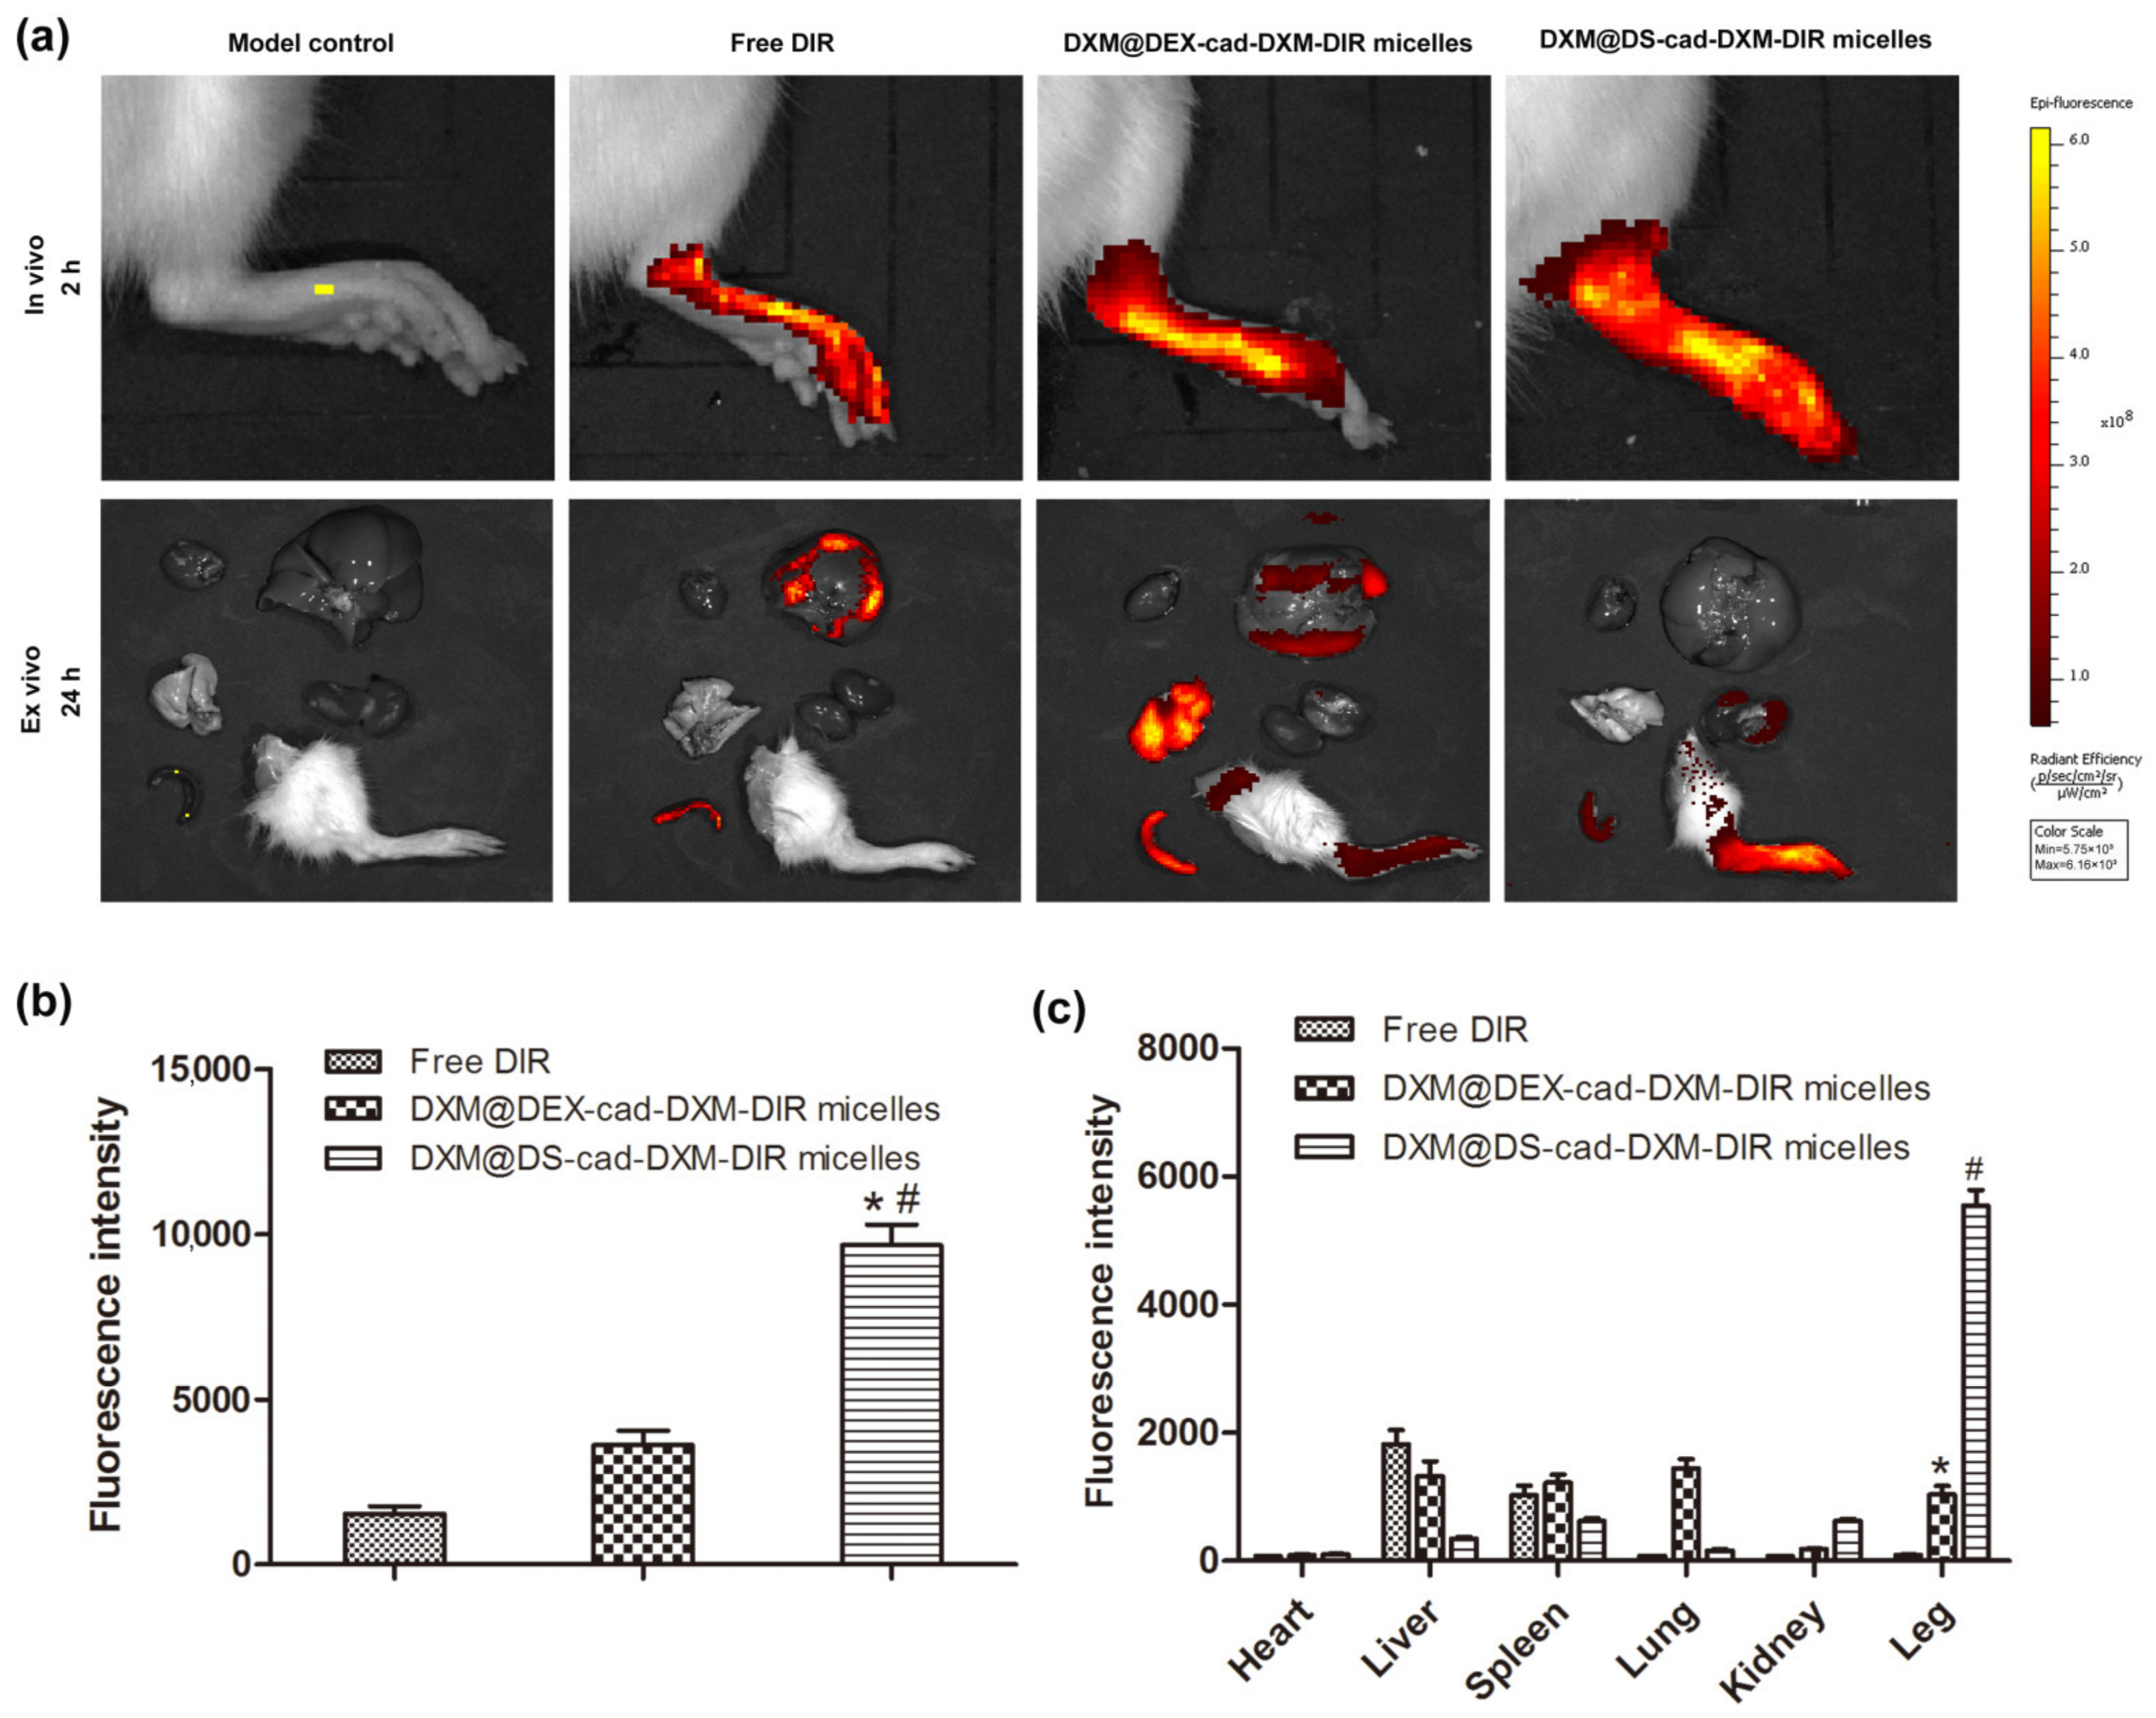

2.5. Selective Biodistribution In Vivo

3.9. Biodistribution of DXM@DS-cad-DXM